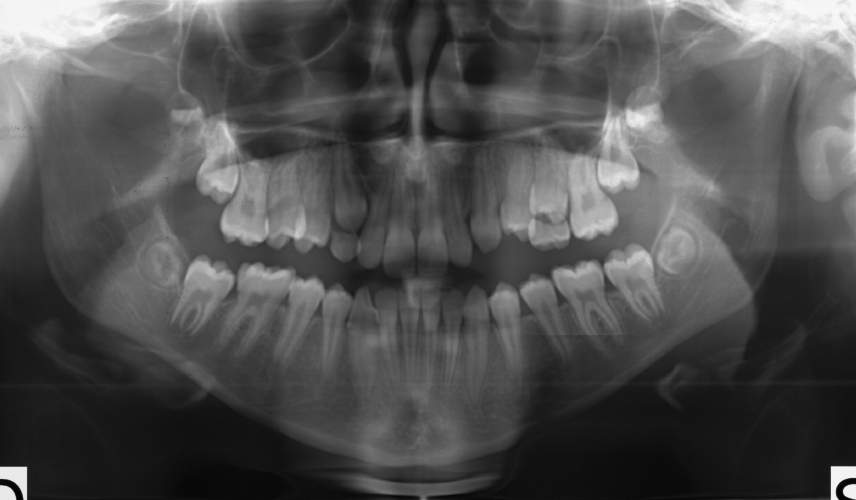

Le apparecchiature radiologiche prese in considerazione sono i radiografici per endorali, gli ortopantomografi, i cefalometri e le Cone Beam Computed Tomography (CBCT).